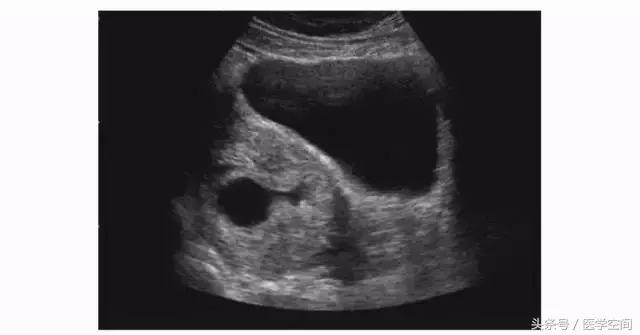

1.2不典型CSP的超声表现

又分为两种类型,第一种为宫腔内见孕囊型,孕囊多位于宫腔下段(较大孕囊可充满整个宫腔),但孕囊部分种植于剖宫产子宫瘢痕处,彩色多普勒超声(CDFI)检查瘢痕部位常可见较丰富血流信号(见图2);第二种为瘢痕部位包块型,子宫剖宫产瘢痕处未见孕囊,可见不均质低回声包块,其周边常可见较丰富血流信号(见图3)。不典型CSP容易漏诊及误诊。

图2不典型CSP的超声表现

图3不典型CSP的超声表现